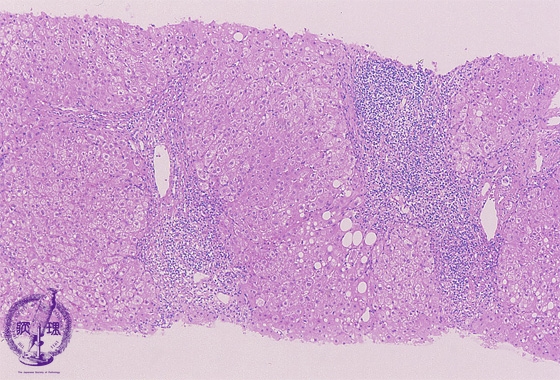

Microscopic image (HE stain, low power view): There is a dense lymphocytic infiltrate with corresponding moderate to marked portal expansion (yellow circle). Fibrosis (blue line) is also seen, and results in disruption of the lobular architecture with segregation of lobules which imparts a nodular appearance in some areas (blue area).